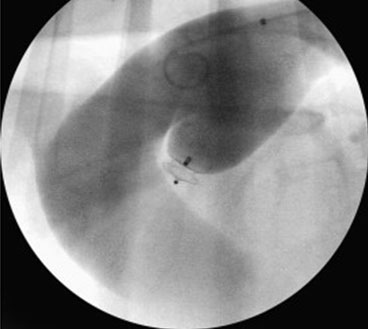

PDA Occlusion

Pulmonic Balloon Valvuloplasty & Stenting

Aortic Balloon Valvuloplasty